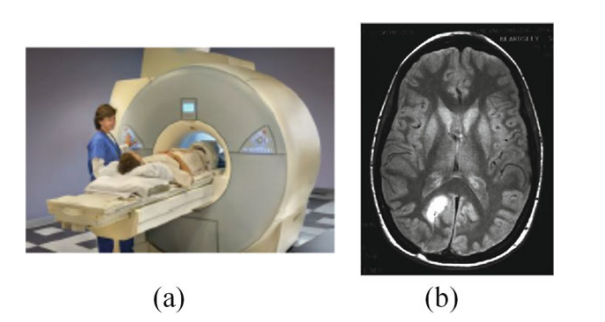

6. Magnetic Resonance Imaging

진동하는 강한 자기장이 인체의 특정 부위에 특정 주파수로 가해지면 인체의 수소 원자가 고주파를 방출하여 인체의 특정 부위의 영상을 형성하고 이를 MRI 기계에 포착한다. MRI 영상 시스템과 뇌종양이 있는 MRI 영상은 각각 그림 (a)와 (b)에 나와 있다.